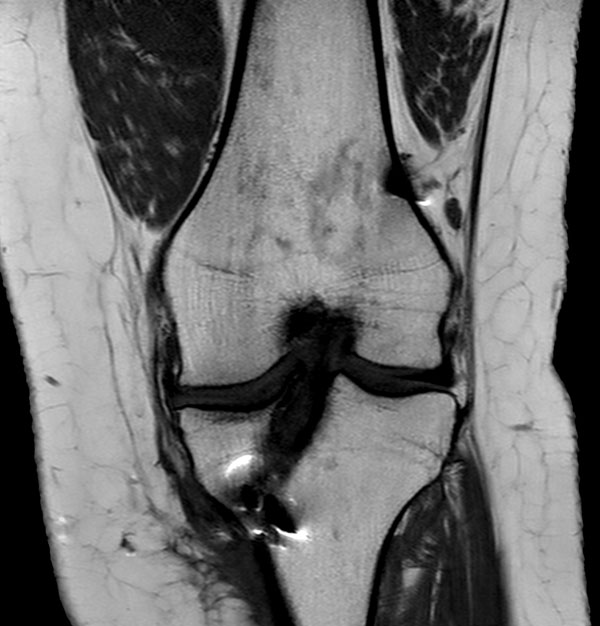

Coronal T1w TSE